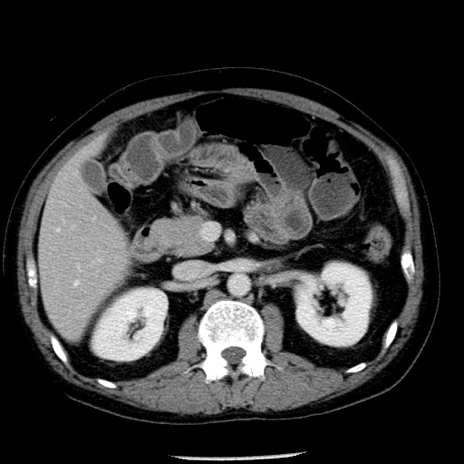

冠状断像

【症例】40歳代男性

【現病歴】2日前から胃痛あり。徐々に周期的な激痛に変化した。本日になっても激痛があるため受診。

【身体所見】意識清明、BT 38-39℃台あり、腹部:膨満、やや硬、右下腹部に圧痛あり。

【データ】WBC 8500、CRP 23.26